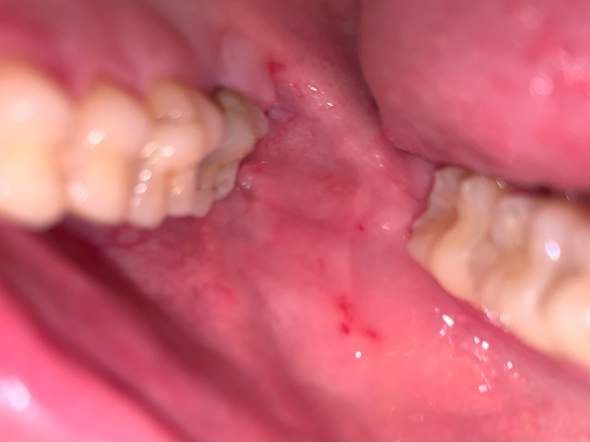

Die roten Punkte die bevorzugt im Mundbereich auftreten sind das Leitsymptom der perioralen Dermatitis. Den Saft lasse ich schon gany weg und er bekommt nur noch warmen oder kalten Tee Wasser etc.

Der Ausschlag kann jucken und dauert etwa fünf Tage. Rote Punkte um den Mund. Auch auf die Wangen u. Brennende rote Haut um die Lippen Hals Augen. Die Erkrankung kann nicht nur in der Mundregion auftreten. Die roten Punkte die bevorzugt im Mundbereich auftreten sind das Leitsymptom der perioralen Dermatitis. Den Saft lasse ich schon gany weg und er bekommt nur noch warmen oder kalten Tee Wasser etc.